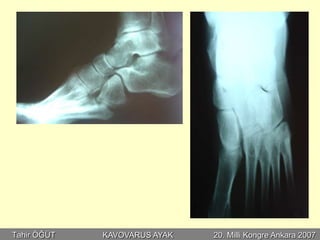

MY, 36 E

EMG:

Sağ: Peroneal yanıt yok

Tibial amplitüd çok düşük

Bilat: GK motor ünite potansiyeli izlenmedi